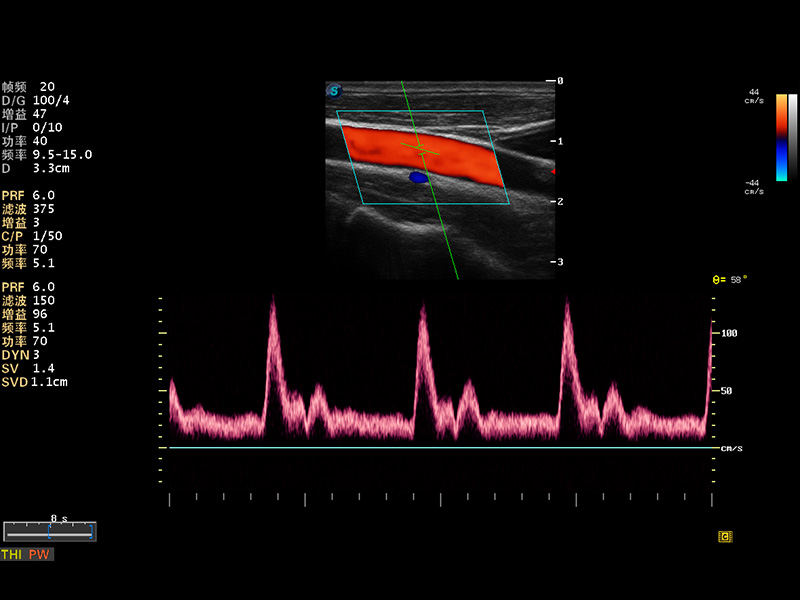

S8 EXP便携式彩色多普勒超声诊断仪是诸侯快讯官网研发的高端全身应用型便携彩超。高通道的VIS平台融合可视化(Visual)、智能化(Intelligent)和人性化(Smart)的特点,配以诸侯快讯官网自主研发生产的探头大家族,使您能够快速、准确的获得病人信息,提高工作效率的同时减轻疲劳。

成像技术